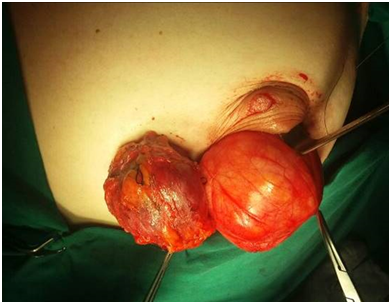

A 47year-old woman with history of a long standing palpable mass on the left breast, which was biopsied on 2006 resulting in hamartoma. She had first degree familiar history of breast cancer with her mother diagnosed younger than 50 \years of age and who later on died of that cause. The patient presented to our office, in June 2016 for progressive growth of her breast tumour. At examination her breasts were fibrous, with a palpable firm and mobile breast mass, not fixed to skin, of 8x6x5cm on the left LIQ, and another large, soft and well defined mass in left LOQ and UOQ of 10x10x5cm, There were no palpable masses in the axilla. On mammography there was a radiolucid well defined breast mass in the left LOQ and UOQ, which was stable in size and shape regarding prior mammogram of twoyears. A new dense, oval and partially defined breast mass was evident in the LIQ (Figure 1). The latter on breast ultrasound corresponded with a hypoechoic and heterogenous nodule with partially defined margins, which measured approximately 7cm. The first lesion was heterogenous and hyperechoic, measured more than 8cm, and was the previously biopsied nodule (Figure 2). She later on underwent a breast MRI that showed a round mass in the LIQ, which was hyperintense in T2, hypointense in T1, had a homogenous enhancement with a plateau curve. In the LOQ there was a well-defined mass, which was heterogenous with fibrous and fatty tissue, and did not enhance with gadolinium (Figure 3). A core biopsy of the two masses was then performed, demonstrating a biphasic fibro-epithelial lesion compatible with a PT at the LIQ, and fibrocystic changes and intraductal hyperplasia without atypia at the LOQ. On August 2016, the patient underwent a partial mastectomy, without incidents, and was sent home on the subsequent day (Figure 4). The definitive biopsy demonstrated that the tumour at the LIQ corresponded to a malignant PT (Figures 5) (Figure 6), and that the LOQ mass was a large breast hamartoma (Figures 7 & Figure 8). Posteriorly, she received 25 radiotherapy fractions, without major adverse effects. She was recently controlled with breast ultrasound and MRI that showed no residual breast lesions.

Figure 4 Partial mastectomy, circumareolar incision, showing the excision of both tumours (left Phyllodes and right Hamartoma).